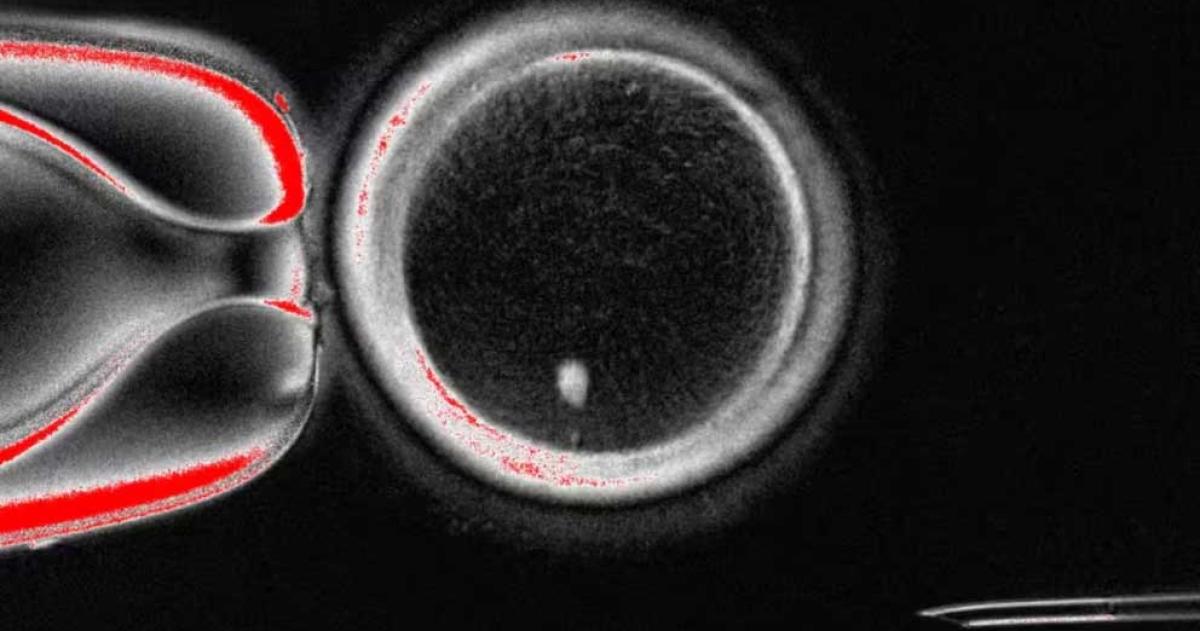

El proceso consistió en extraer el núcleo de una célula cutánea (con 46 cromosomas) e insertarlo en un óvulo donado que había sido previamente enucleado. Para evitar que esta nueva célula duplicara su material genético, los científicos desarrollaron un protocolo experimental que imita los pasos de la meiosis natural (el proceso de división celular que genera gametos).

Con esta estrategia, se generaron 82 ovocitos funcionales. Aunque la proporción es baja, un 9% de estos ovocitos consiguió desarrollarse hasta la fase de blastocisto (equivalente al sexto día tras la fecundación), el momento habitual para la transferencia al útero en un tratamiento de fecundación in vitro. Este hito constituye la primera evidencia de que la técnica puede funcionar en humanos, si bien la mayoría de los embriones desarrollados mostraron anomalías cromosómicas.